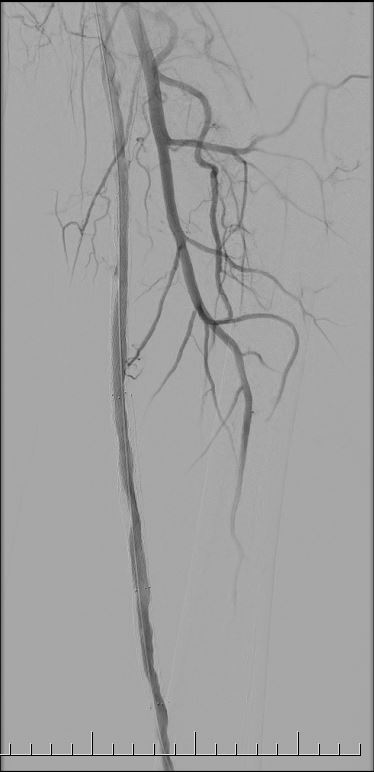

La sala donde te realizarán la angioplastía se encuentra a baja temperatura. Este procedimiento se efectúa con anestesia local y comienza con la introducción de un catéter por punción en una de las arterias del brazo, la muñeca o la ingle, de acuerdo a las características de cada persona y a la zona a estudiar (arteria aorta abdominal o arterias renales, de los miembros inferiores o de otros territorios).

Este catéter llega hasta las arterias que se van a tratar y una vez allí se inyecta una sustancia de contraste, que permite visualizar las obstrucciones existentes. A través de este catéter se inserta un balón, que se expande en el sitio obstruido y luego se retira, dejando lugar para la eventual colocación de un stent.